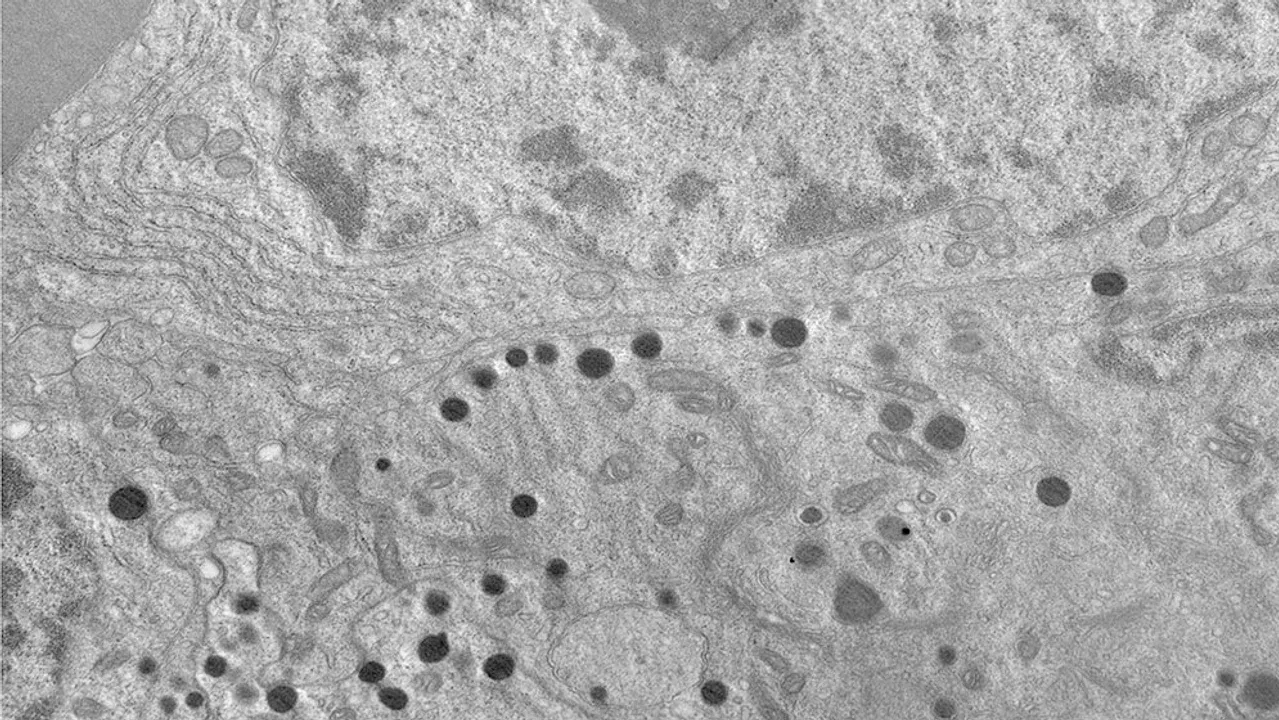

Especialistas del Consejo Nacional de Investigaciones Científicas y Técnicas (CONICET), de la Universidad Nacional de Córdoba (UNC) y del Hospital Privado Universitario de Córdoba identificaron un nuevo blanco terapéutico prometedor para pacientes con un tipo de tumor hipofisiario donde el 50 por ciento de los pacientes no responden adecuadamente a tratamientos actuales. El avance se describe en la revista Neuro oncology.

Los tumores neuroendocrinos hipofisarios (PitNETs) representan el segundo tipo más común de tumores intracraneales y uno de sus subtipos, los tumores somatotropos constituyen el segundo más frecuente. Para este tumor, la “cirugía transesfenoidal” es el tratamiento de primera línea, pero un número significativo de pacientes requiere tratamiento adicional. Los tratamientos farmacológicos se basan en análogos de somatostatina como el Octreótido (OCT), pero el 50% de los pacientes no responde adecuadamente a esta terapia.

Ahora, especialistas del CONICET, de la UNC y del Hospital Privado Universitario de Córdoba comprobaron que la inhibición de la proteína SHP2 reduce significativamente el crecimiento de los tumores somatotropos en modelos preclínicos, señalándola como un nuevo blanco terapéutico prometedor para los pacientes en los que el fármaco de uso común, el OCT, no ejerce efectos terapéuticos.

“El trabajo preclínico lo comprobó y ahora se abren las puertas para profundizar esta línea de investigación con el fin de avanzar hacia el desarrollo de nuevas posibilidades terapéuticas para los pacientes en los que no funcionan las terapias convencionales”, indicó Juan Pablo Petiti, líder del estudio e investigador del CONICET.